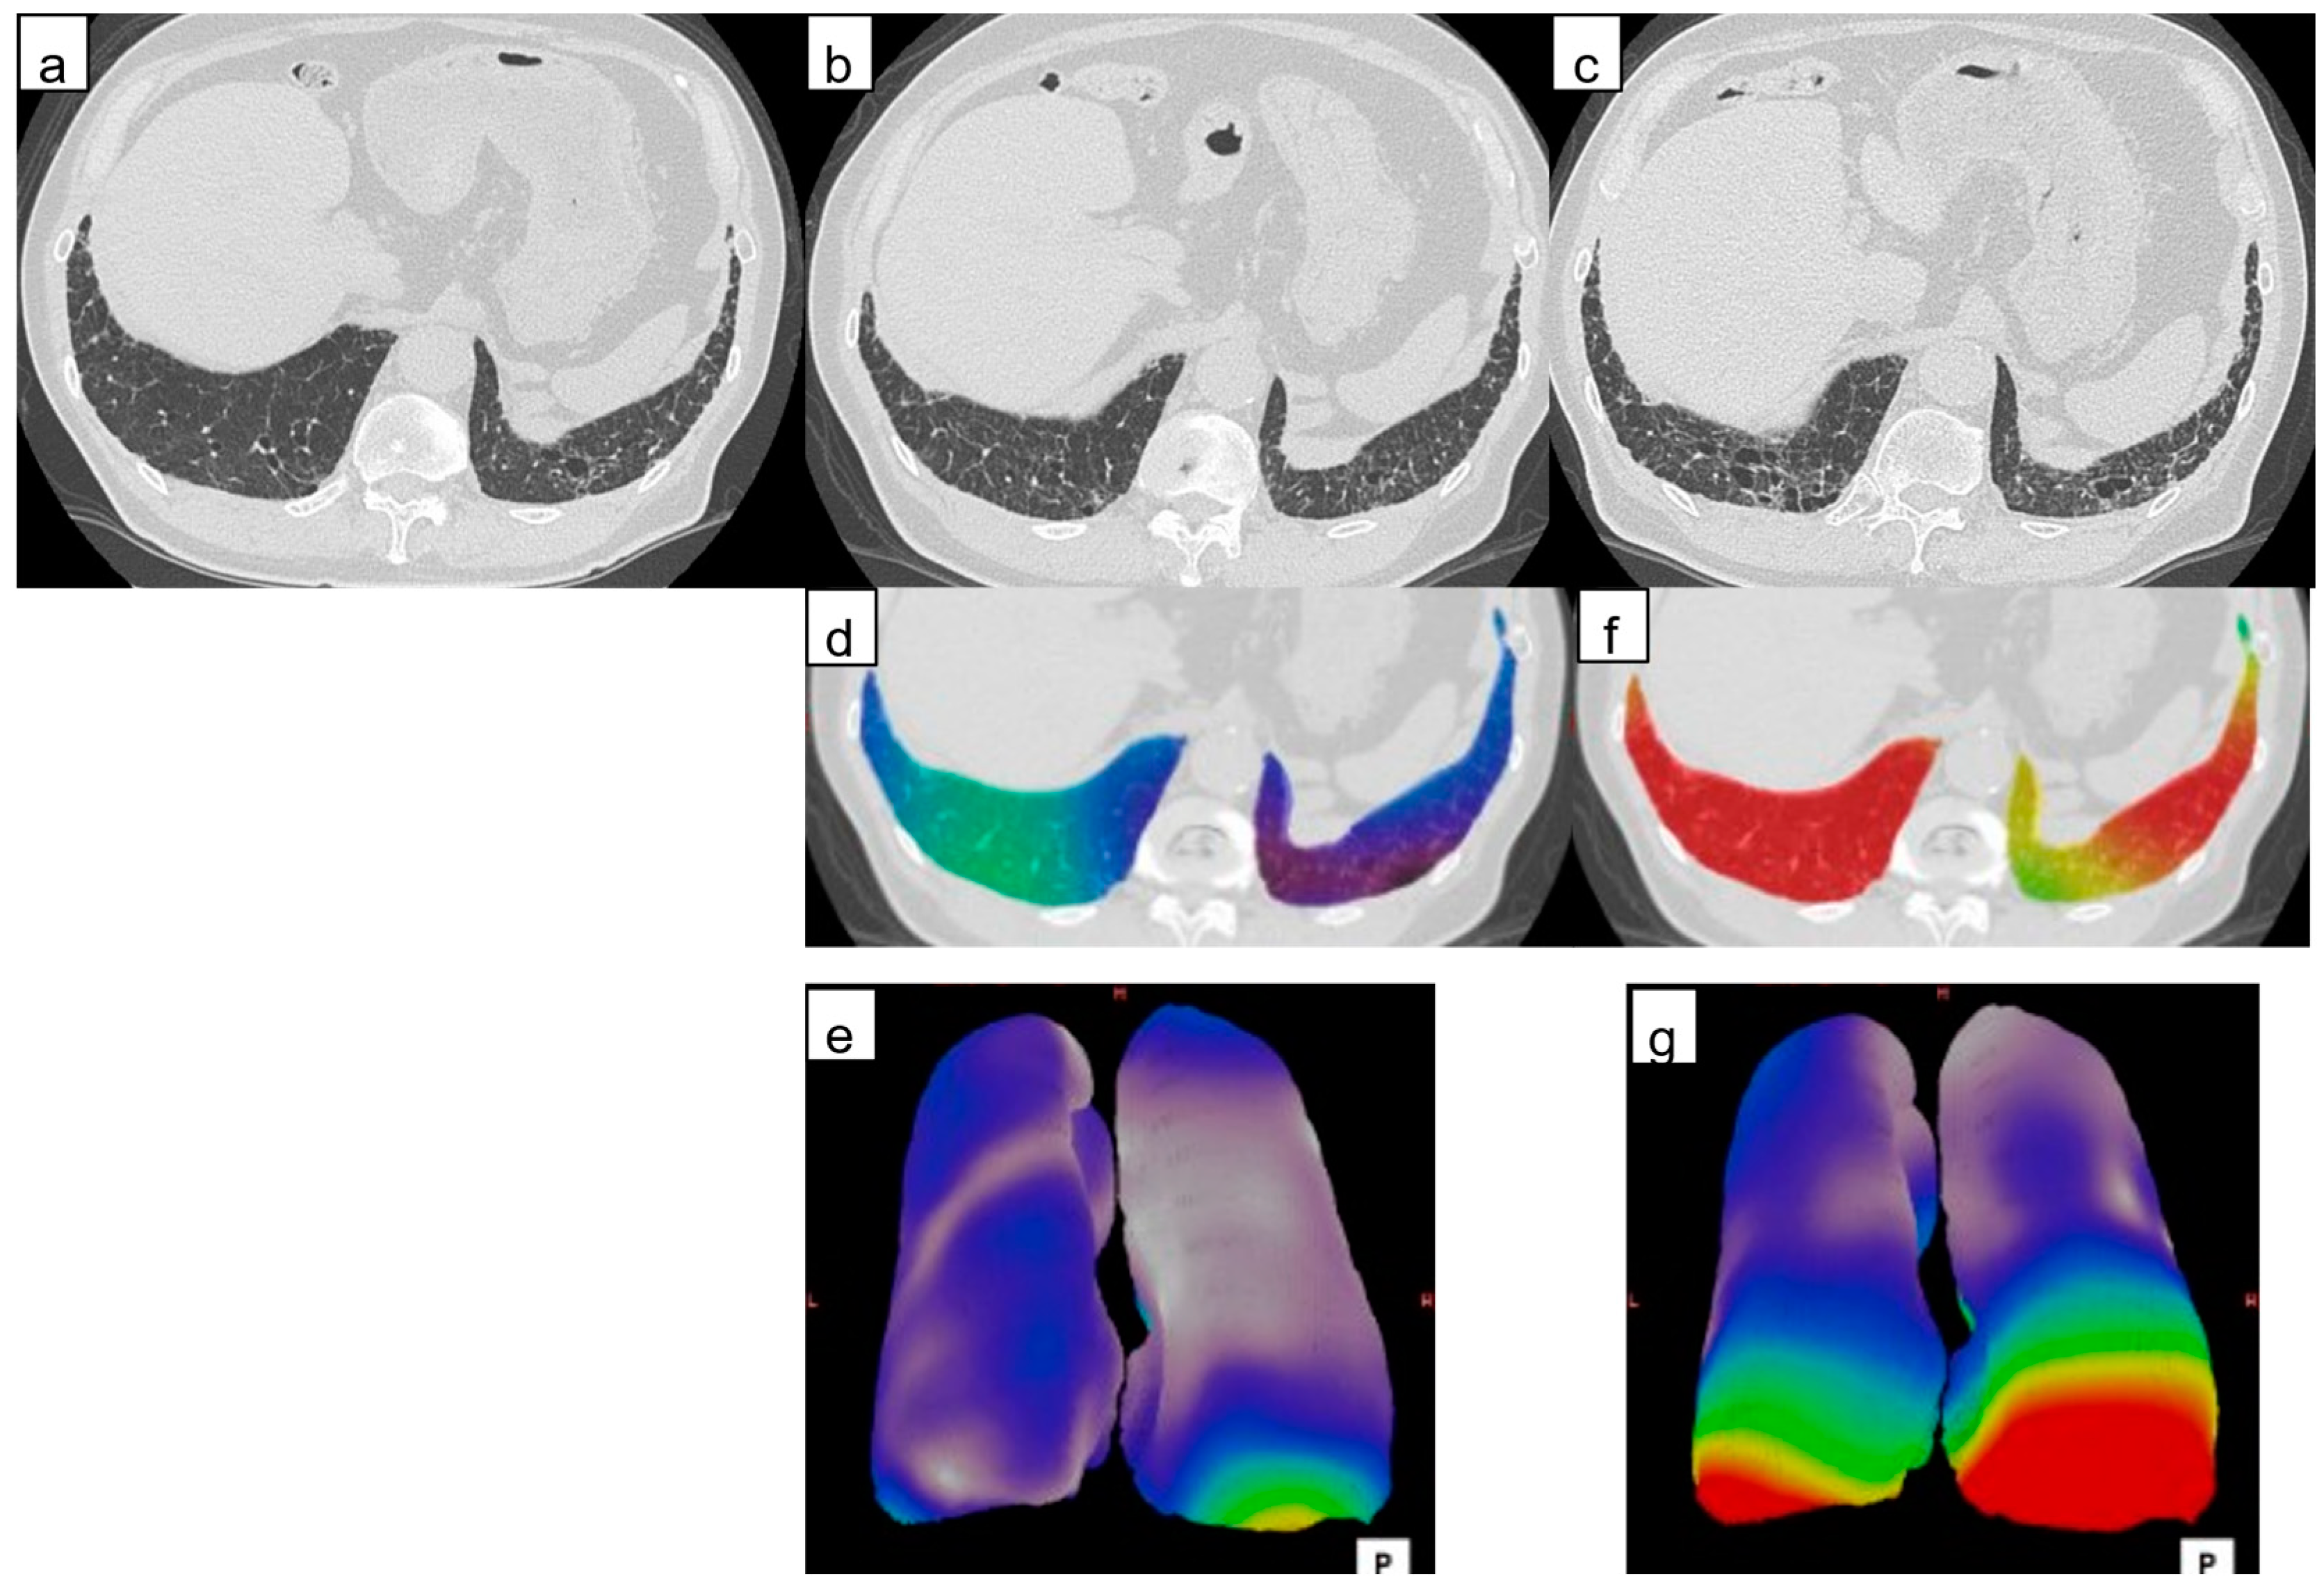

2.3.1. Architectural Distortion Measurement by 3D-AD

3.2.1. Architectural Distortion Measurement by 3D-AD